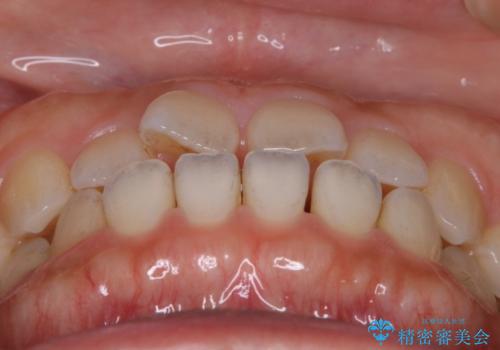

- 矯正治療を主訴にご来院されました。

すきっ歯と噛み合わせの治療をしたいとのことで、インビザラインを用いて矯正治療を行うこととなりました。

すきっ歯の場合、ガタつきを治したりするのに必要なスペースが最初から空いているため、そのスペースを利用して比較的短期間で効率よく治療を進めることが可能となります。

初診時の写真では一見噛み合わせには問題がないように見えても、実際に精密な検査を行うと改善すべき点が見つかる場合も多くあります。